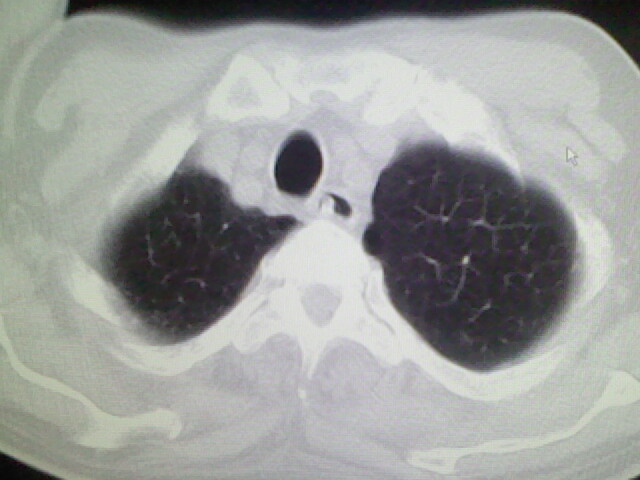

男,70岁,脑出血,长期卧床,左侧背部可触及肿块

右肺病灶考虑炎症性。

慢性间质性炎症,与老年患者长期卧床相关,胸壁软组织及肋骨未见异常。

考虑右肺及左肺下叶炎症。

考虑右肺及左肺下叶慢性炎症。

右侧肺部见片状密度增高影,边缘模糊。考虑炎症。另食管壁增厚。

右肺上叶前段病呈楔形,其尖端指向肺门,考虑肺动脉栓塞可能性大.